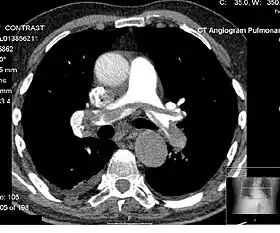

![]() Example of a CTPA, demonstrating a saddle embolus. The white area above the center is the pulmonary artery, opacified by radiocontrast. Inside it, the grey matter is blood clot. The black areas on either side are the lungs, with around it the chest wall. | |

A normal CTPA scan will show the contrast filling the pulmonary vessels, appearing as bright white. Any mass filling defects, such as an embolus, will appear dark in place of the contrast, filling/blocking the space where blood should be flowing into the lungs.

On CTPA, the pulmonary vessels are filled with contrast, and appear white. Any mass filling defects (embolus or other matter such as fat) appears darker. Ideally, the scan should be complete before the contrast reaches the left side of the heart and the aorta, as this may mean contrast has drained from the pulmonary arteries, or require a larger dose of contrast media.[12]